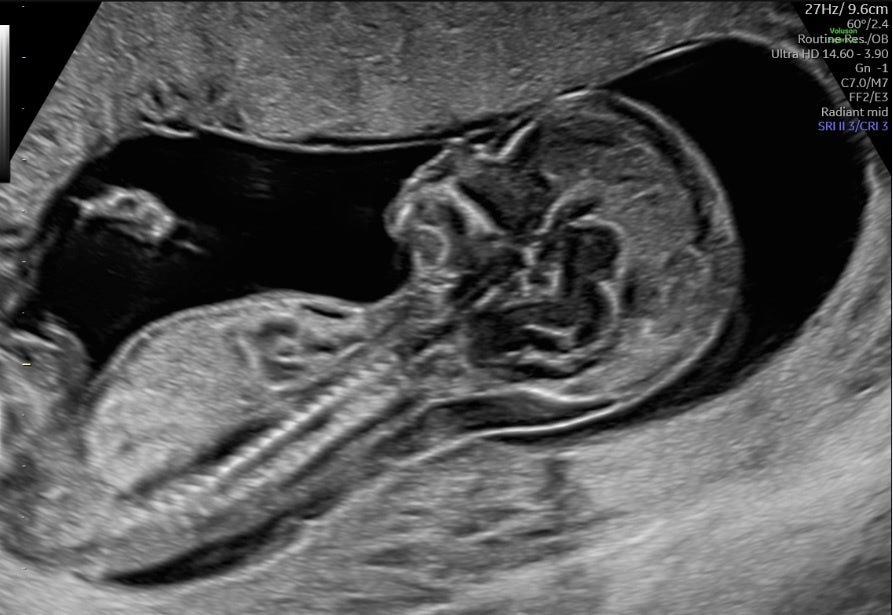

Voluson Expert 22では、より膨大な情報を高速処理可能な次世代エンジンLyric Architectureを搭載したことで、ソフトウェア制御されたビームフォーミングを実現。ハードウェア制御の限界を超え、格段に向上したペネトレーション、分解能、フレームレートを提供します。また、従来のVoluson製品では活用できなかった、新たなレベルの画像処理が可能となり、分解能に特化したイメージングモードから、深部感度に特化したイメージングモードまで、観察条件に大きく左右されることのない、明瞭な画像を提供します。

分解能に特化したイメージングモード:UltraHD with Radiant